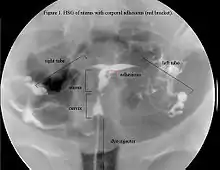

يشكل تاريخ حدوث الحمل المتبوع بالتمدد والكشط (D & C) الذي يؤدي إلى انقطاع ثانوي للطمث أو قلة الطمث أعراض نموذجية. فالرحم هو المعيار الذهبي لتشخيص هذا المرض.[15] التصوير عن طريق التخطيط الصوتي للرحم أو تصوير الرحم و البوق يكشف عن مدى تشكل الندبة. بينما لا يمكن الاعتماد على الأمواج فوق الصوتية لتشخيص متلازمة آشرمان. تظهر دراسات هرمون مستويات طبيعية متناسقة مع وظيفة الإنجاب.